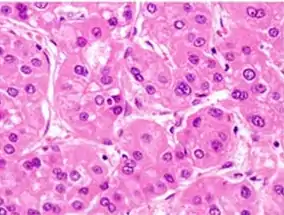

Microscopically, the four architectural and cytological types (patterns) of hepatocellular carcinoma are: fibrolamellar, pseudoglandular (adenoid), pleomorphic (giant cell), and clear cell. In well-differentiated forms, tumor cells resemble hepatocytes, form trabeculae, cords, and nests, and may contain bile pigment in the cytoplasm. In poorly differentiated forms, malignant epithelial cells are discohesive, pleomorphic, anaplastic, and giant. The tumor has a scant stroma and central necrosis because of the poor vascularization.[39] A fifth form – lymphoepithelioma like hepatocellular carcinoma – has also been described.[40][41]

Micrograph of hepatocellular carcinoma. Liver biopsy.

Well-differentiated HCC

Moderately differentiated HCC.

Poorly differentiated HCC